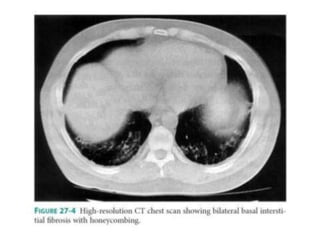

PULMONARY MANIFESTATION

• PLEURITIS with or without pleural effusion.

• When Mild, may respond to treatment NSAIDs

• When More Severe, patients require glucocorticoid

therapy.

• Pulmonary Infiltrates also occur as a manifestation of

active SLE

• Life-threatening pulmonary manifestations include

interstitial inflammation leading to fibrosis, shrinking

lung syndrome, and intraalveolar hemorrhage

PULMONARY MANIFESTATION • PLEURITISwith or without pleural effusion. • When Mild, may respond to treatment NSAIDs • When More Severe, patients require glucocorticoid therapy. • Pulmonary Infiltrates also occur as a manifestation of active SLE • Life-threatening pulmonary manifestations include interstitial inflammation leading to fibrosis, shrinking lung syndrome, and intraalveolar hemorrhage